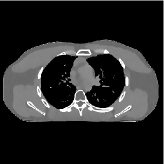

This section compares the reconstruction quality and runtime among the proposed MBIR method, PWLS-ST-, and other three MBIR methods, PWLS-EP, PWLS-DL, and PWLS-ST-. Table I shows that, for both 2D and 3D sparse-view CT reconstructions of the XCAT phantom, the proposed PWLS-ST- model outperforms PWLS-EP and PWLS-ST- in terms of RMSE. In addition, PWLS-ST- using a square transform (of size ) achieves lower RMSE than PWLS-DL using an overcomplete dictionary (of size ) for 2D sparse-view reconstructions. Fig. 3(a) and Fig. 4 show the reconstructed images for 2D and 3D phantom experiments, with different reconstruction models and different number of views. (See the corresponding error maps in the supplement.) The proposed PWLS-ST- consistently gives more accurate image reconstructions compared to other MBIR methods. Specifically, PWLS-ST- has smaller errors in the heart region (see zoom-ins in Fig. 3(a)) of 2D reconstructions than PWLS-DL and PWLS-ST-. In addition, compared to PWLS-ST-, PWLS-DL and PWLS-ST- have some ringing artifacts around the edges with high transition, e.g., edges between air and soft tissues. (See a comparison of profiles of PWLS-ST- and PWLS-ST- in the supplement.) In particular, PWLS-ST- and PWLS-DL give more visible ringing artifacts for 2D reconstruction from fewer views, and PWLS-ST- has these ringing artifacts for 3D reconstructions regardless of the number of views (see zoom-ins in Fig. 4). Table II reports runtimes of different MBIR methods in reconstructing the -views XCAT phantom scan. (FBPConvNet is a non-MBIR method and its runtime for processing a image is approximately one second with a TITAN Xp GPU.) While providing better reconstruction quality, the proposed Algorithm 1 of PWLS-ST- has shorter runtime compared to the algorithms of PWLS-DL and PWLS-ST- in Section III-A. Similar to the PWLS-EP algorithm, the reconstruction time of the PWLS-DL, PWLS-ST-, and PWLS-ST- algorithms can be further reduced by using ordered subsets [51].

| (b) 3D axial cone-beam CT experiments |